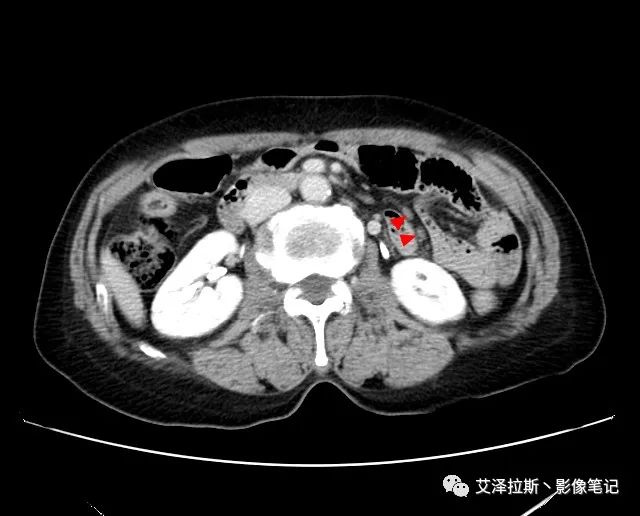

【影像所見】 胃竇部狹窄,胃壁環形增厚,小彎側見一巨大潰瘍,周圍伴“環堤征”,漿膜面不完整,胃周脂肪見網格狀條索影,病灶與肝臟左葉、胰腺鉤突脂肪間隙消失,增強掃描病灶明顯強化。引流區內約15個區域淋巴結受累。

【診斷意見】 胃竇部胃癌(T4N3期) 該病例腫塊突破漿膜層,與肝臟左葉、胰腺鉤突分界不清,脂肪界面消失,定為T4期; 受累及的淋巴結為15個區域,定為N3; 有無遠處轉移尚不明確,所以M期暫時無法確定。